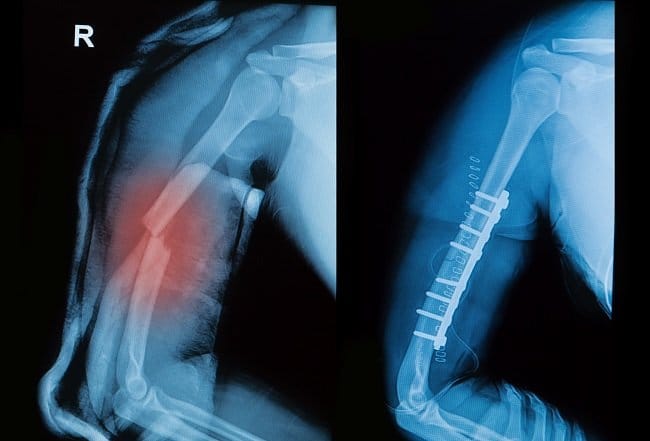

- Foto Rontgen, untuk melihat lokasi patah tulang

Operasi

Jika patah tulang humerus tidak dapat diobati dengan pemasangan gips, dokter dapat menyarankan prosedur operasi. Beberapa teknik operasi yang dapat dilakukan dokter adalah:

- Pemasangan pen, untuk menahan ujung tulang yang patah agar tetap pada tempatnya